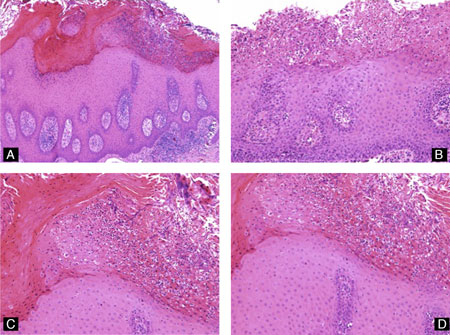

LS часто ассоциируется с dVIN. Классический вид LS характеризуется истончением эпидермиса, потерей ребер, базальным вакуолярным изменением и широкой полосой гомогенизированного коллагена в дерме. Также могут наблюдаться полосообразный лимфоцитарный инфильтрат и вариабельный отек, особенно на ранних стадиях.

LS с гиперплазией, дискератозом и паракератозом (обычно в виде столбцов над кожными сосочками) называется гипертрофическим LS. В этом случае наблюдается минимальная базальная цитологическая атипия, отсутствие скученности и минимальное или отсутствие митозов.